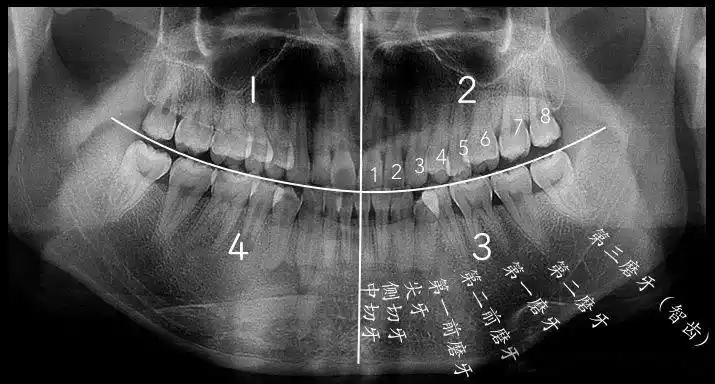

三分钟教你看懂牙片! 牙齿中间出黑线? 食物残渣爱塞缝?

全景片上智齿怎么看

看牙片不求人手把手教你自己看牙片

牙片详解,教你看懂牙片!_口腔_牙齿_全景

牙片详解,教你看懂牙片!

2,全景片判断牙齿的拥挤程度.

怎么看口腔全景片